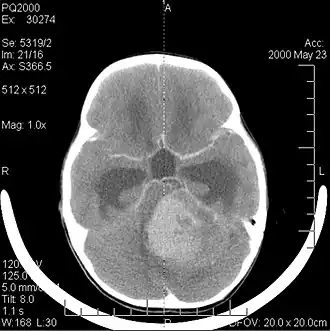

![]() Компьютерная томография головы больного с медуллобластомой | |

Компьютерная томография

В типичных случаях на КТ медуллобластомы определяются как объёмные образования круглой или овальной формы, которые неоднородно накапливают контрастное вещество и располагаются в проекции червя мозжечка. Данные новообразования смещают IV желудочек вентрально. Достаточно часто определяются кисты (до 65 %) и микрокальцинаты[20].